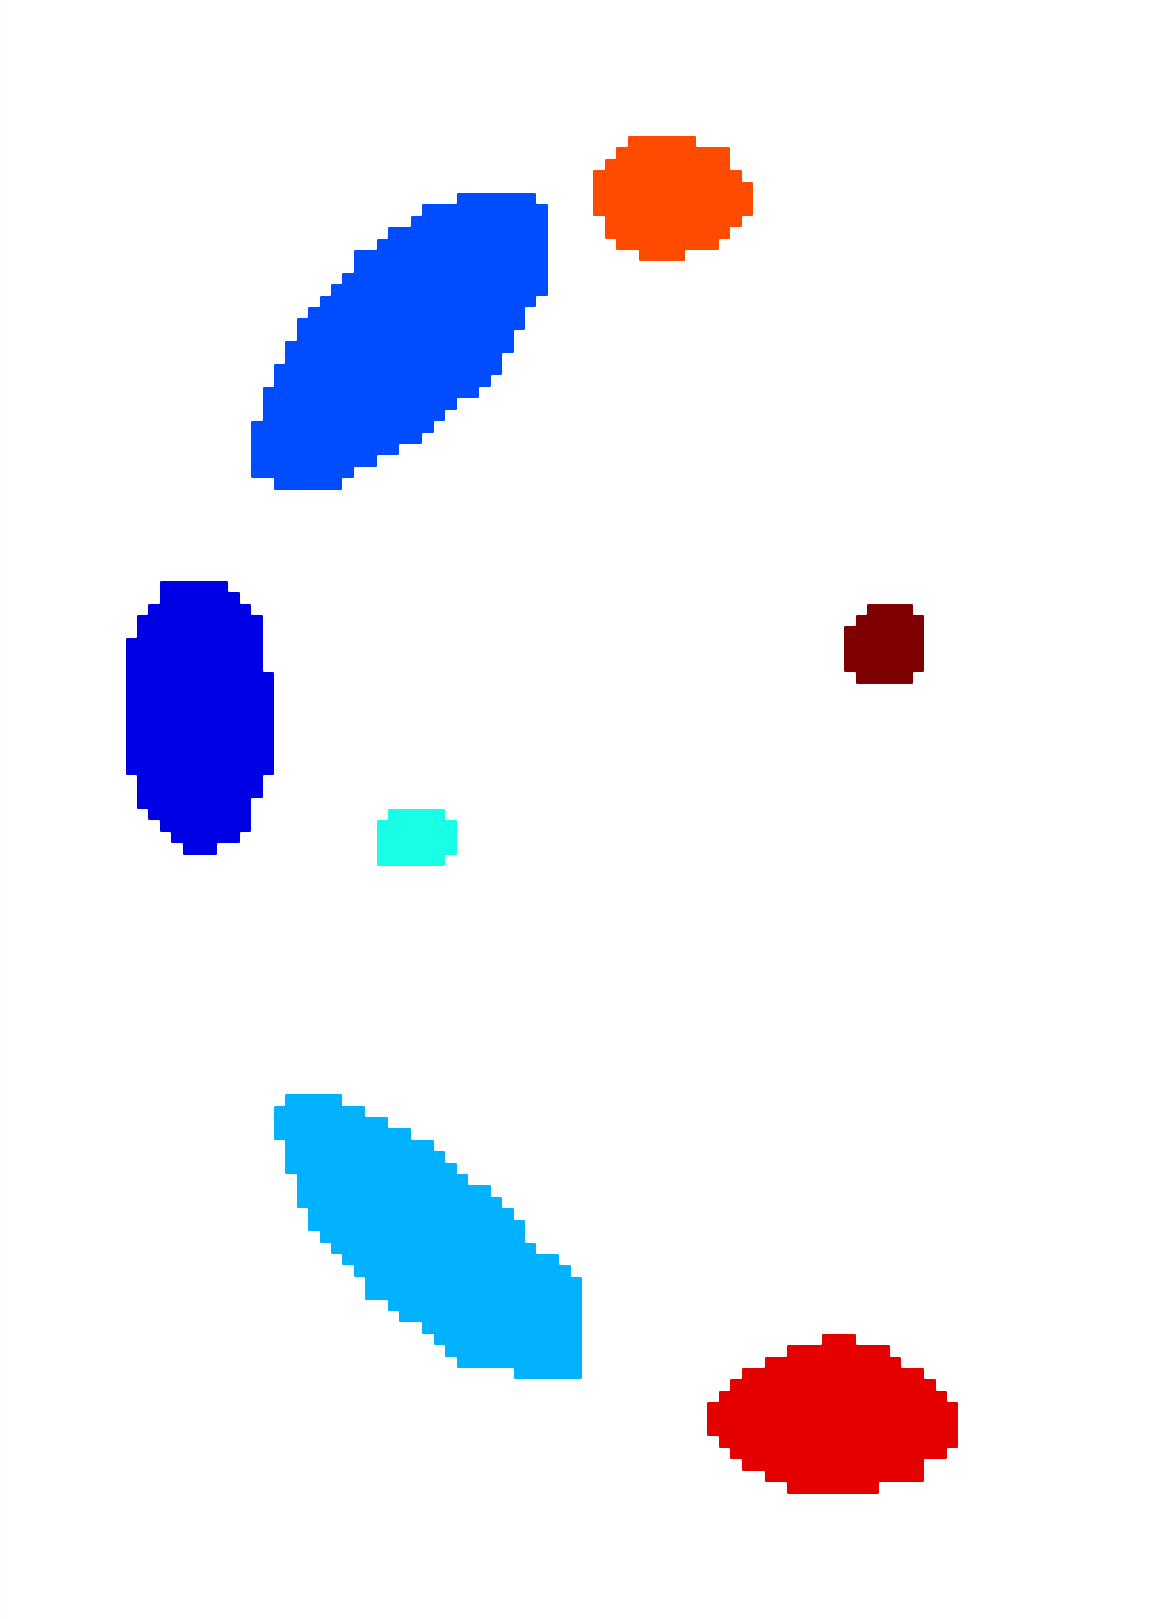

The scalar vesselness responses of both HCP and PC images are determined using the state-of-the-art Frangi filter (FFR) [8], and Optimally Oriented Flux (OOF) [12]. Also, the connected vesselness map (CVM) and the associated tensor field (TF) are synthesized for the same dataset using VTrails. The connectedness of the considered scalar maps is qualitatively assessed and the TF is inspected as proof of concept in section 3.1.

3.1 Connectedness of the Vesselness Map

Fig. 3 shows the connectedness of vessels recovered from state-of-the-art vascular enhancers and curvilinear ridge detectors FFR and OOF together with the proposed CVM for the synthetic HCP and the real PC images.

On the synthetic phantom, FFR shows a fragmented and rough vesselness response in correspondence of irregularly shaped sections of the structure. Also, the response at the bifurcation is not smoothly connected with the branches (triangular loop). Conversely, OOF recovers the phantom connectedness at the branch-point, and the vesselness response is consistent along the tortuous curvilinear section, however ghosting artifacts are observed as the shape of the phantom becomes irregular (C-like) or differs from a cylindrical tube. Also, close convoluted structures, which change scale rapidly in the HCP, produce inconsistent responses of OOF (fig. 3). CVM shows here a strongly connected vesselness response in correspondence of both regular and irregular tubular sections, with local maxima at structures’ mid-line. The connectedness of the structures is emphasized regardless the complexity of the shape, and it resolves spatially the tortuous curvilinear ‘kissing vessels’ without additional ghosting artifacts, despite the smooth profile.

Similar results are observed on the PC dataset: FFR has a poor connected response in the noisy and low-resolution image. Vessels are overall enhanced, however thin and fragmented structures remain disconnected. Overall, the vesselness response is not uniform within the noisy structures, where maximal values are often off-centred. A more consistent response is obtained from OOF, where the connectedness of vessels is improved. Maximal response is observed at the mid-line of vessels, however, noise rejection is poor. CVM strongly enhances here the vessel connectivity. The fragmented vessels of PC have a continuous and smooth response in CVM with higher values and a more defined profile. Large vessels shows solid connected regions with local maxima at mid-line as in OOF. Conversely from OOF, CVM shows improved noise rejection in the background.

The respective tensor fields (TF) synthesized on both HCP and PC show consistent features. The TF’s characteristics are in line with the connectedness of CVM: enhanced and connected vessels are associated with high anisotropy, whereas background areas show a predominant isotropic component.